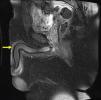

MRI findingsSagittal MRI sequences of the penis revealed a thrombosis in the superficial vein of the penis under the skin on the dorsal penis (Figs. 2 and 3). Doppler USG of the penis supported the diagnosis with the lack of flow in the superficial vein of the penis due to thrombosis. The Doppler USG also showed low velocity and highly resistant flow in the cavernous arteries.

The diagnosis of PMD using MRI is a controversial subject. The improved image quality in MRI and the use of godalinum during the procedure as an angiographic agent allowed the evaluation of early arterial and late venous phases. However, this procedure can only be recommended for cases in which a diagnosis or differential diagnosis could not be established. Systemic fibrosis is the most important factor limiting the use of MRI-angiography. There is only one case report in the literature that was diagnosed using MRI-angiography. This procedure was reported to be helpful in the diagnostic process due to the coexistence of various diseases and symptoms.14 The currently reported case is valuable for the demonstration of the possibility of diagnosing the condition without using godalinum to avoid the risk of systemic fibrosis.